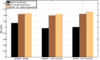

| (a) Box plot of the registration error | (b) Close-up view of (a) |

| Figure 2: Spatial distances (in millimeters) between corresponding landmarks before and after the registration process. | |

For the assessment of the proposed method, we carry out a comparison with the purely intensity-based variational method recently presented by the authors of this work in [26]. This CR-based approach was reported to outperform publicly available state-of-the art methods such as Elastix and ANTs in the medical setting. As can be seen in Fig.1, the proposed framework shows excellent results for the three considered registration scenarios (arterial-portal, arterial-non-contrast and portal-non-contrast), reaching average values of 1.47, 1.44 and 1.52 bits in terms of mutual information, corresponding to the arterial-portal, arterial-non-contrast and portal-non-contrast cases, respectively; this represents a mean improvement of 28.9%, 48.45% and 51.16% in relative terms of mutual information, thus outperforming the CR-based registration algorithm, which achieves a mean improvement of 26.48%, 44.22% and 43.25%, respectively. Additionally, due to the analogous behavior (i.e., comparable final values of mutual information) of the proposed method in the three scenarios, all available experiments can be grouped into one ensemble in order to assess a more comprehensive validation of the actual registration error. A ground truth was established by an expert in the form of identifiable anatomical locations (landmarks) for all experiments. The registration errors were then obtained by computing the spatial distance between the corresponding landmarks in the reference and registered template datasets. Figures Fig.2(a) and Fig.2(b) show through box plots the registration error (in millimeters) achieved by the methods under comparison, gathering the results from the three considered registration scenarios. These box plots collect the final spatial distances between corresponding landmarks, along with the median distance error and its statistical significance (notch showing the 95% confidence interval of the true median). According to Fig.2(b), the proposed method significantly improves on the registration error of the CR-based approach, since it reduces the initial median error from 9.50 mm to a residual median distance between landmarks of 1.41 mm, decreasing at the same time the outliers occurrence.